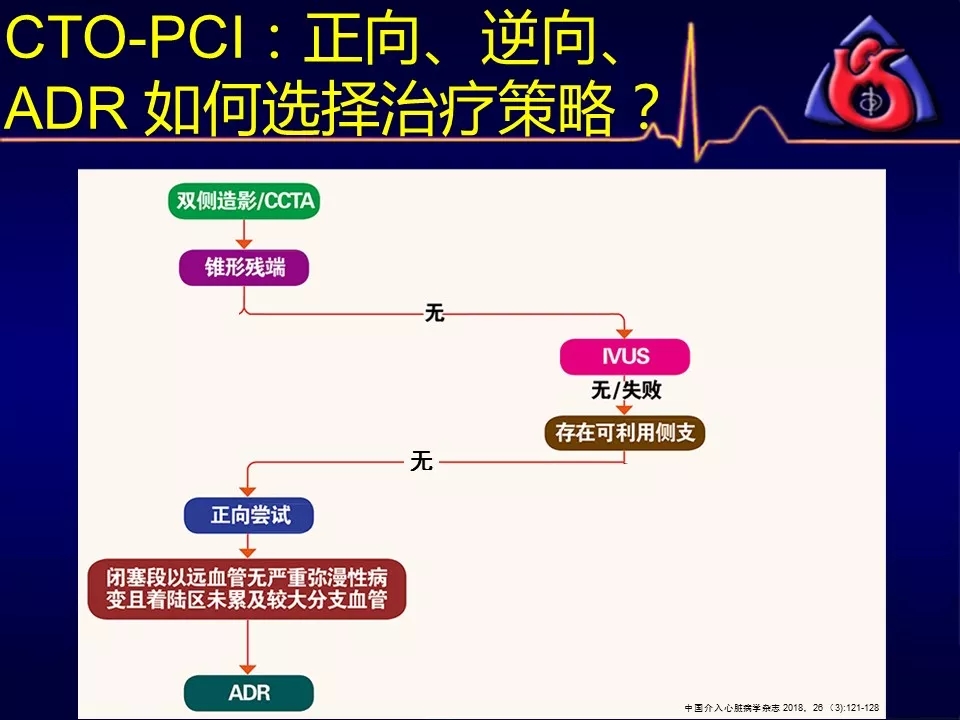

如何选择正向、逆向、IVUS指引及ADR技术?